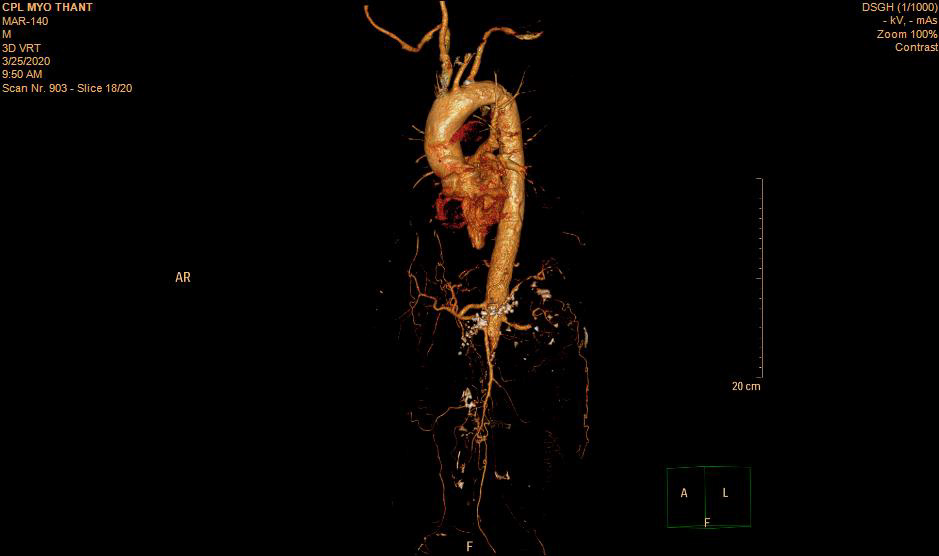

As his left femoral artery pulsation became weak and thus, CT Aortogram was done (4 weeks after symptom onset of right femoral artery occlusion). It revealed extensive thrombosis with complete obstruction of abdominal aorta starting below the level of celiac trunk- both renal arteries and both iliac arteries. The calcifications of the arterial wall at aortic arch, thoracic and abdominal aorta and both iliac vessels were seen too. (Figures 5-11) Thus, he had severe atherosclerosis due to hypertension and heavy smoking. Occlusion of both renal arteries explained his high blood pressure. The cholesterol and uric acid level were normal. He was treated with atorvastatin, aspirin, clopidogrel, antihypertensives, wound care, physiotherapy, intensive nursing care nutritional support and antibiotics.

This patient had on going ischaemia as the wound was not healing well and diminished left femoral pulsation. And it was a clinical clue to arterial obstruction at higher level – above femoral artery. It was proved by CT angiogram.

Regarding the aetiology of arterial occlusion in this 43-year-old patient, relatively young age, severe atherosclerosis was the main culprit as there were extensive atheromatous plaque in wall of the whole aorta and it was aggravated by smoking and hypertension. It was the main reason for reporting this case. Moreover, It was not due to COVID-19 infection because it was excluded initially though there were few case reports having deep vein thrombosis, pulmonary embolism and arterial thrombosis due to COVID-19 infection [11-13].